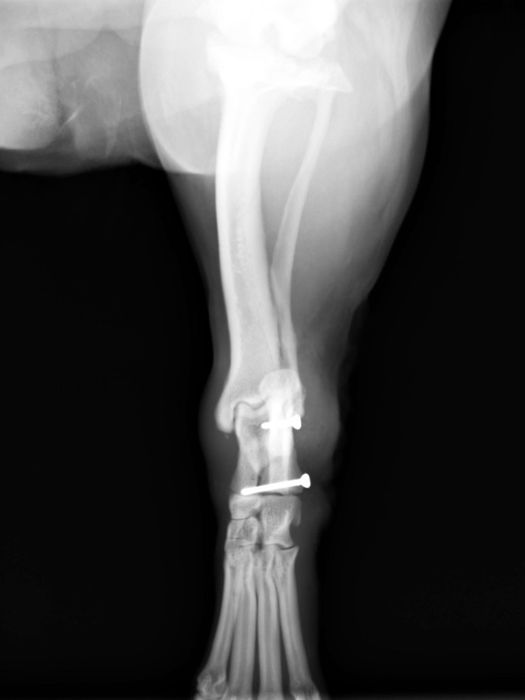

●創外固定器

ネジ山があるピンを骨に刺入し、皮膚の外で連結バーとクランプを使用して固定を行います。

●髄内ピンと創外固定器の併用法(リニア型創外固定TypeⅠa "tie in")

●手根関節脱臼